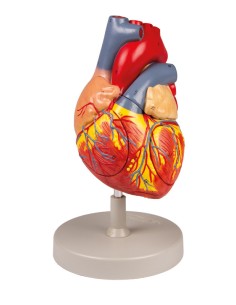

Dal cranio in 22 parti con incastri magnetici ai modelli di colonna vertebrale, da quelli di articolazioni a quelli di cuore, ogni pezzo della nostra collezione è progettato per un’immersione totale nello studio dell’anatomia umana. I nostri modelli, realizzati tramite scansioni di ossa vere, garantiscono un’esperienza tattile autentica e una fedeltà di peso quasi identica agli originali.

Essenziali per studenti e professionisti, i nostri modelli anatomici sono strumenti didattici che permettono di osservare le strutture anatomiche con precisione, eliminando la necessità di dissezioni o studi invasivi. Sono inoltre utili per spiegare ai pazienti le patologie, rendendo la comunicazione più efficace e risparmiando tempo prezioso.